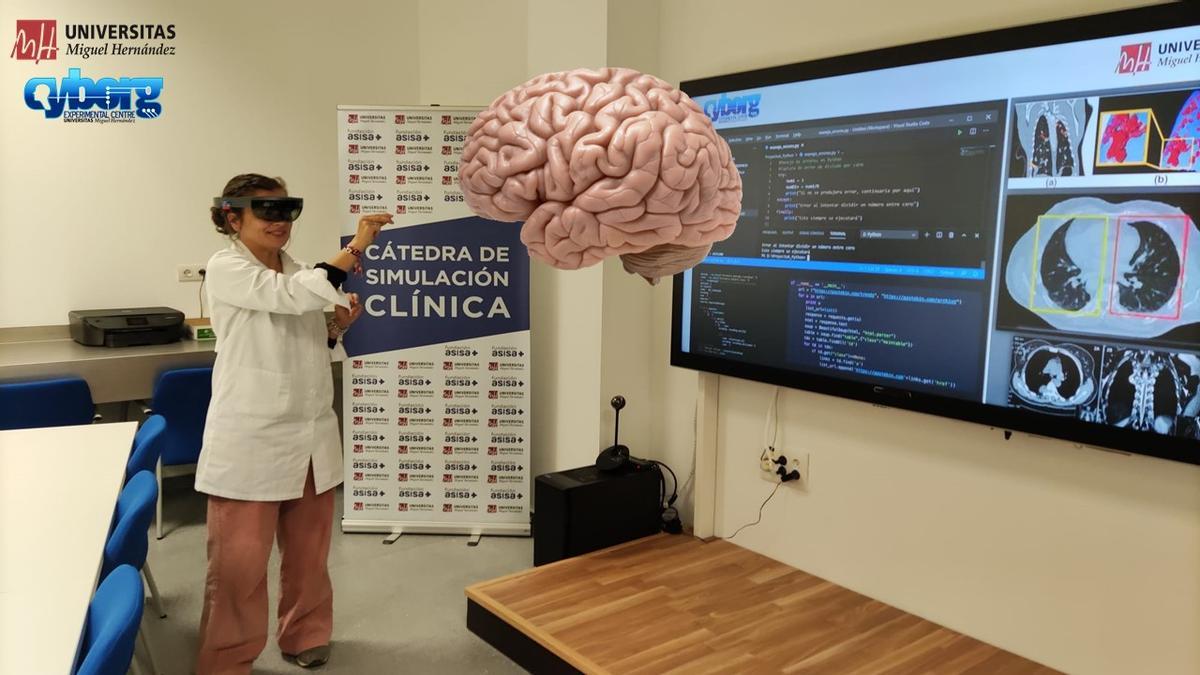

Cátedra de simulación clínica de la Facultad de Medicina / INFORMACIÓN

Este mismo departamento está iniciando un programa piloto de aprendizaje con realidad virtual inmersiva y tridimensional para algunas asignaturas de Medicina, Podología, Fisioterapia y Terapia Ocupacional en el que el estudiante elige el foco, por ejemplo, para hacer un vendaje, estudiar huesos o músculos. "Estamos iniciando el programa para ver si se aprender mejor con menor coste" que otras prácticas en Anatomía.

Sistemas que se utilizan en el proyecto Cyborg de Anatomía